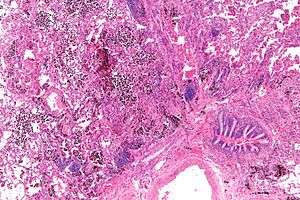

| Micrograph showing a pulmonary haemorrhage. H&E stain. | |

Pulmonary hemorrhage (or pulmonary haemorrhage) is an acute bleeding from the lung, from the upper respiratory tract and the trachea, and the alveoli. When evident clinically, the condition is usually massive.[1] The onset of pulmonary hemorrhage is characterized by cough productive of blood (hemoptysis) and worsening of oxygenation leading to cyanosis.[1] Treatment should be immediate and should include tracheal suction, oxygen, positive pressure ventilation, and correction of underlying abnormalities (e.g. disorders of coagulation). A blood transfusion may be necessary.[1]